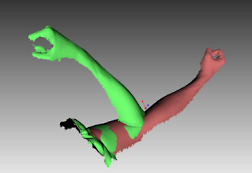

特集 ハンディ3Dスキャナーをリハビリで利用する

1. 従来のマニュアル測定方法に代え、非接触ハンディ3Dスキャナーで関節の曲がり状態を調べる。

ハンディ3Dスキャナーは静止した物だけでなく、動く(移動する)対象物も撮影して、画面ごとにサーフェースモデルを作成します。変化する体(腕や背中など)を撮影し、リハビリでの改善状況の把握に役立てます。また、部品の変位移動量(振動するケーブルや部品の挙動など)を3D解析することで、これまで実行できなかった製品のシミュレーションが可能となります。